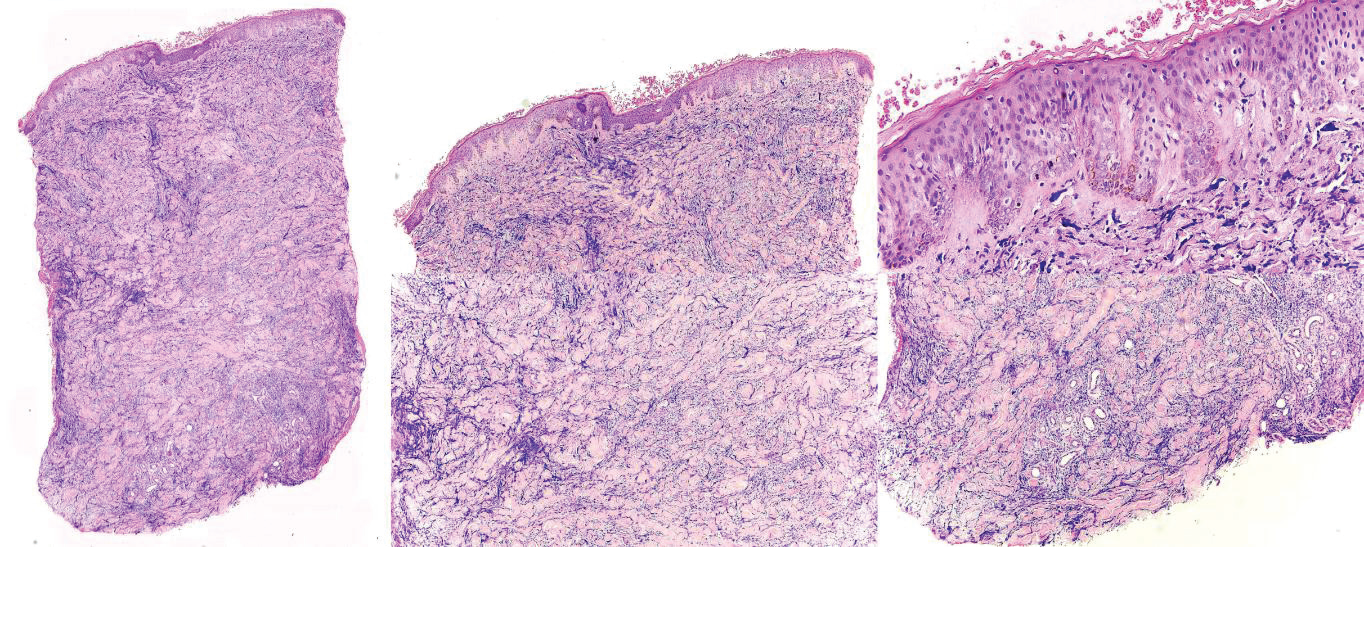

On dermatologic examination, the patient presented with multiple, discrete, round, firm, erythematous to violaceous papules and plaques on the chest, back, and bilateral upper and lower extremities [Figure 1]. The initial clinical differential diagnoses were leukemia cutis, erythema nodosum, fixed drug eruption, arthropod bite reaction, and allergic contact dermatitis. He underwent a 4 mm skin punch biopsy on the chest. Haematoxylin and Eosin-stained sections revealed orthokeratosis, and an acanthotic epidermis that was slightly papillomatous with basal layer hyperpigmentation. In the dermis are diffuse infiltrates of atypical leukemic and myeloblastic cells in between thickened collagen bundles as well as surrounding adnexal structures and neurovascular bundles. [Figure 2]. The specimen was negative for CD3, CD20, Myeloperoxidase (MPO), and CD117 [Figure 3A-D]. Meanwhile, it was positive for CD34 and CD68 (Figure 3E, Figure 3F). The histopathologic examination and immunohistochemical staining were consistent with leukemia cutis.

Figure 2: Haematoxylin and Eosin-stained sections. A. Pathology in the entire

dermis (scanning magnification). B. The epidermis is acanthotic and slightly

papillomatous with basal layer hyperpigmentation (10X magnification). C. The

stratum corneum is orthokeratotic. Grenz zone is noted (40X magnification).

D. In the dermis are diffuse infiltrates of atypical leukemic and myeloblastic

cells in between thickened collagen bundles (10x magnification). E.

Surrounding adnexal structures and neurovascular bundles are appreciated

(10x magnification).